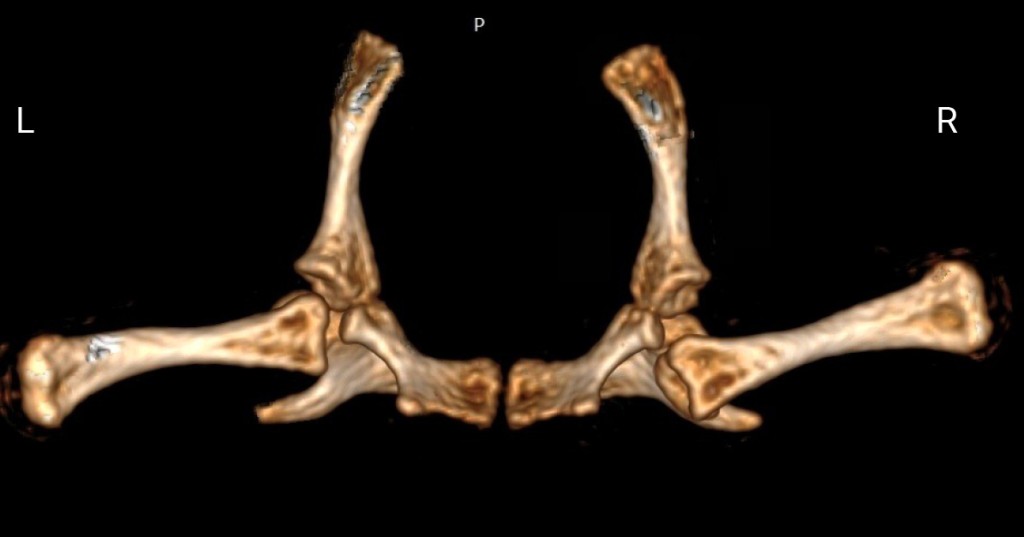

На дорсальных рентгенограммах определялось вероятное вентральное смещение головки бедренной кости из вертлужной впадины. Для подтверждения диагноза «вентральный вывих головки бедренной кости» животному провели компьютерную томографию. Данная процедура была проведена на аппарате Philips MX 16. Сканирование было выполнено в краниокаудальном направлении в положении пациента лежа на пластроне, животное было помещено в закрытый пластиковый бокс 200 × 10 мм, анестезия при исследовании не применялась. Параметры КТ: время вращения трубки 0,6 сек., 134 mAs, 120 kV, поле зрения 180 мм, размер матрицы 1024 × 1024, костное окно. Были выполнены мультипланарные реконструкции в аксиальной, дорсальной и сагиттальной плоскостях в костном окне. По результатам КТ было подтверждено вентральное смещение (вывих) головки правой бедренной кости из вертлужной впадины (фото 1, 2).